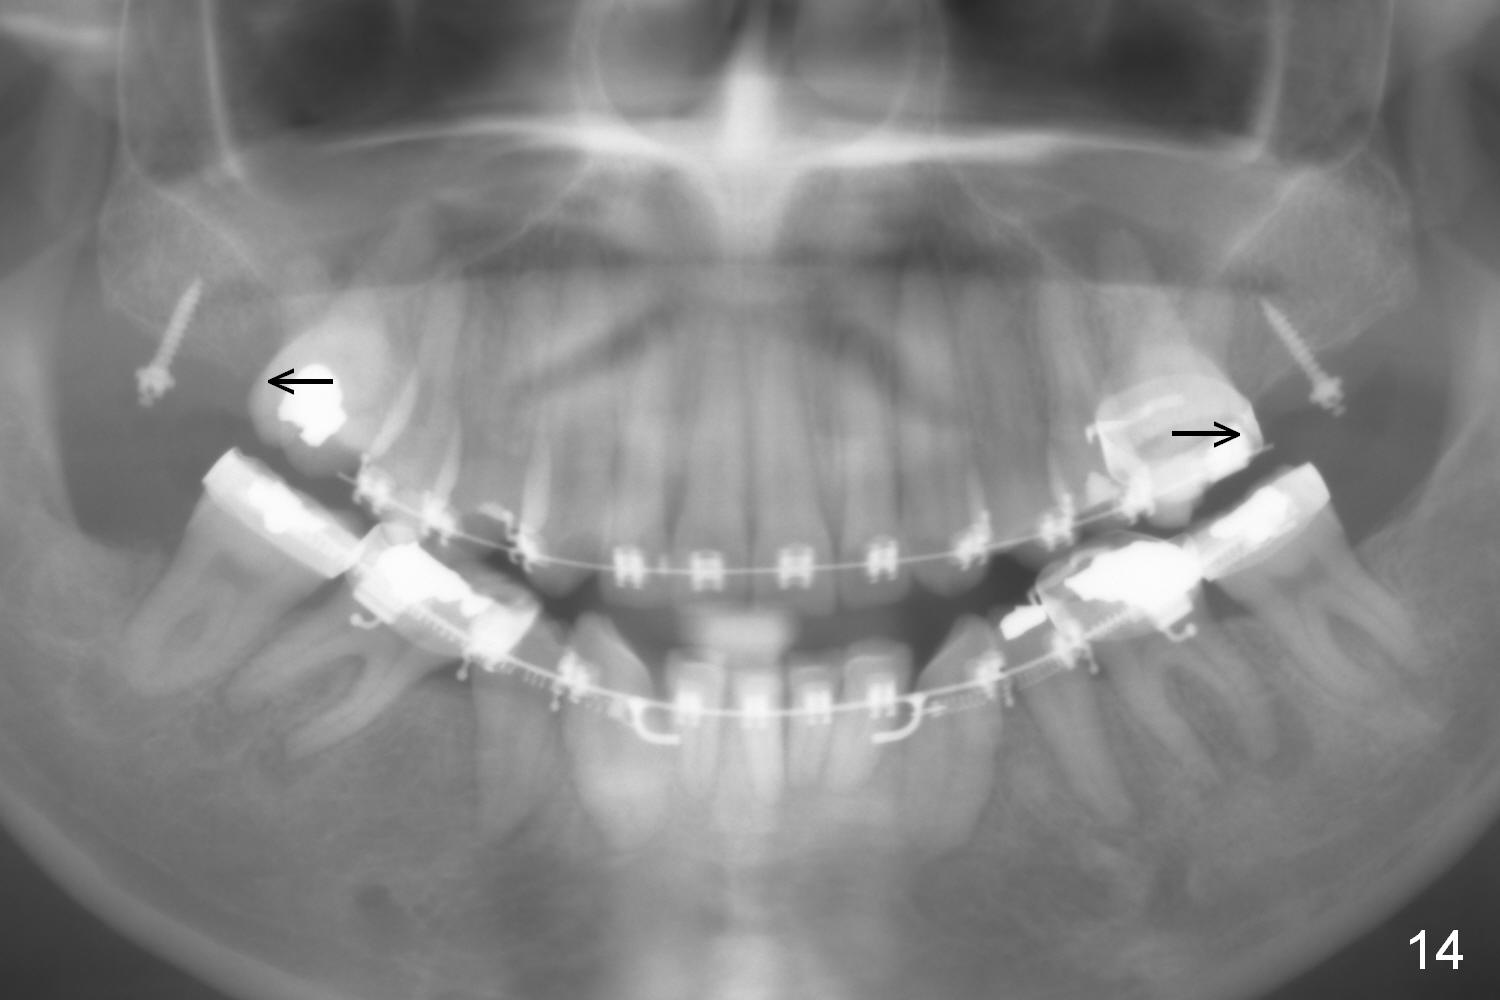

On March 9, 2016 (11.5 months of treatment), periodontal abscess develops around UR6 (Fig.11 (palatal view) *). It appears that the molar band as well as the buccal tube (Fig.12 *) is embedded into the gingiva. One week after band removal (as well as posted wire and closed coil springs), the infection resolves (Fig.14). As compared to preop Panoramus (Fig.13), the upper arch distalization is mainly at the crown level (Fig.4 arrows). The miniimplants should be placed higher (at the zygomatic arch); the post should be taller. Therefore the roots can be distalized as well (click the link below).